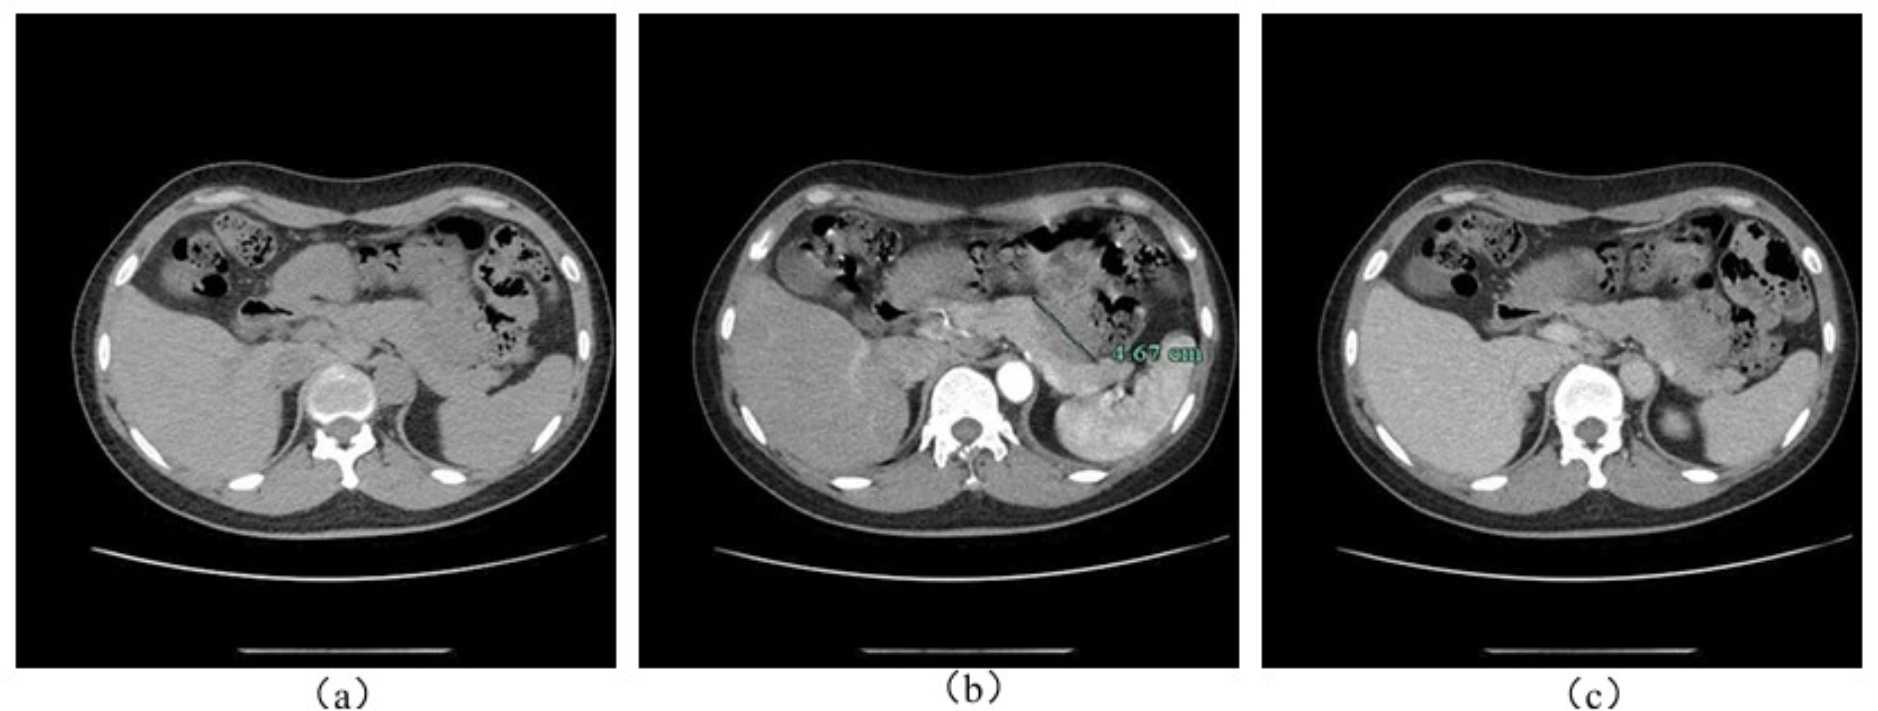

患者女性,49岁,因“腹痛20天”入院,腹痛位于剑突下,阵发性,进食后出现,持续数小时后缓解。患者既往患有高血压、高血脂及颈动脉硬化,药物治疗。起初患者于消化内科接受解痉、护胃、抗感染治疗,未见好转。实验室检查无殊,腹部B超见41*18 mm低回声区,边界尚清,可见点状血流信号。完善检查,CT平扫 + 增强扫描提示胰腺体尾部可见不规则软组织密度团块影,大小约47*35 mm,增强呈渐进式中度强化,内见坏死,与周围脏器边界欠清(如图1)。MRI平扫 + 增强提示肿块位于胰腺体尾部,与胃小弯毗邻,T1WI呈低信号,压脂T2WI呈混杂稍高信号,实性部分弥散受限,动脉期病灶呈不均匀低强化,门脉期实性部分进一步强化,与胰腺及胃分界欠清(如图2)。首先考虑消化系统恶性肿瘤。

注:(a) 平扫:瘤体呈低密度影,边界欠清;(b) 动脉期:瘤体呈中度不均匀强化,内见坏死;(c) 门脉期:瘤体呈渐进式不均匀强化。

Figure 1. Preoperative abdominal enhanced CT examination

1. 患者术前腹部增强CT检查